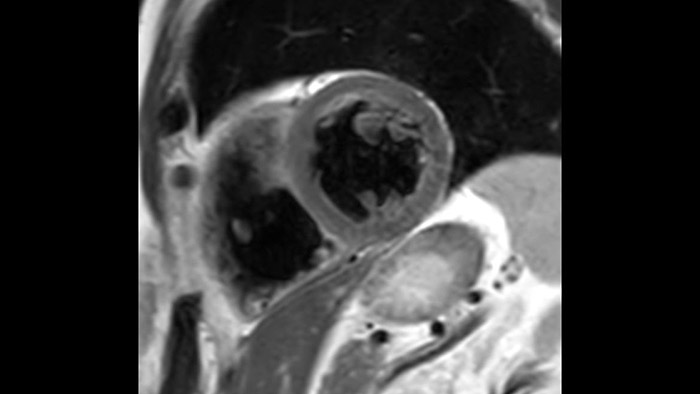

MR exams for patients with MR Conditional cardiac devices

Pacemakers are not a hard contra-indication for CMR, there are many MR Conditional pacemakers. ScanWise Implant3 offers step-by-step guidance to enter condition values of the implant manufacturer and automatically apply these values to the entire examination.  Simplifying your scanning process for patients with MR Conditional implants.